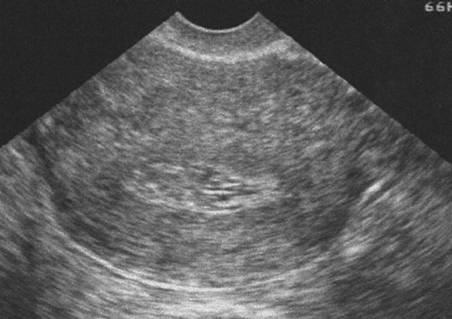

Endomètre Tamoxifène (Cliché : Dr. C. TALMANT)